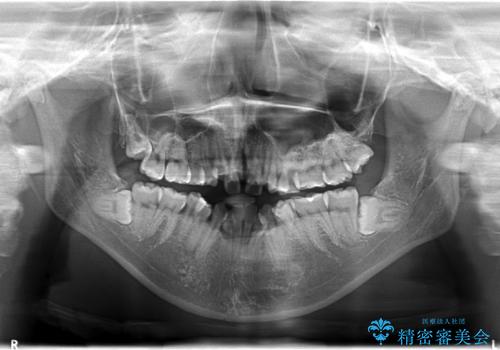

- 20代女性

- 4年

- 30回以上

- 上顎の骨格性拡大+両側第1小臼歯抜歯 によりスペースを獲得、フルリンガルによるワイヤー矯正を計画した。

骨格的要因を背景にもつ不正咬合のため、歯列矯正単独での改善は困難と判断しましたが、患者さんとの相談の結果、歯列矯正単独で可能なところまで一緒に頑張りましょうということで、治療をすすめました。